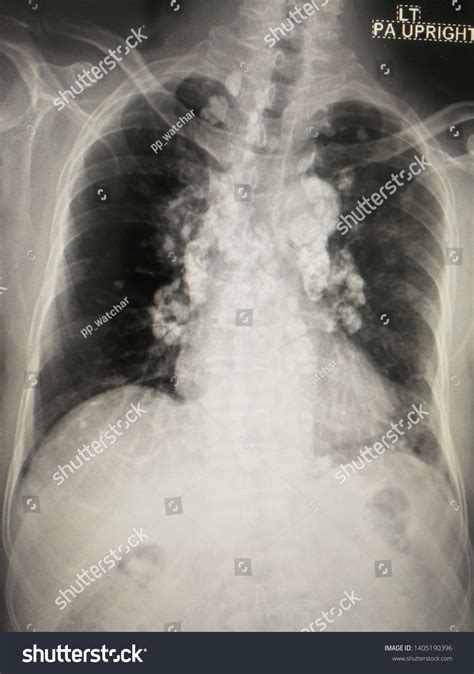

Diagnosing conditions involving Hilar Lymph Nodes often requires imaging techniques such as chest X-rays, CT scans, or PET scans. These imaging methods can help visualize the size and shape of the lymph nodes, providing valuable information for diagnosis and treatment planning.

• Chest X-ray: This imaging technique can provide a basic view of the lungs and Hilar Lymph Nodes, helping to detect enlargement or other abnormalities.

• CT Scan: Computed tomography (CT) scans offer a more detailed view of the lungs and Hilar Lymph Nodes, allowing for better visualization of any abnormalities.